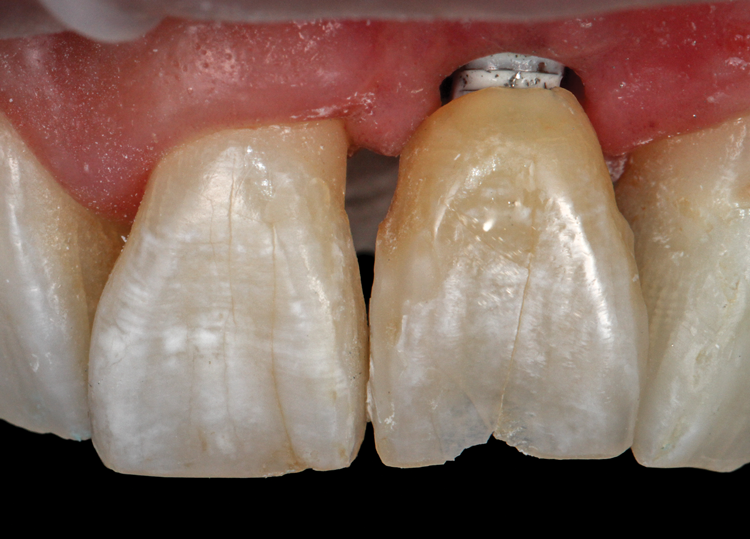

(45.) A patient presented for the replacement of the maxillary left central incisor with a bonded pontic made from the natural tooth, which was removed.

Figure 45

(46.) Occlusal view of the implant after placement.

Figure 46

(47.) The primary stability of the implant was confirmed to be sufficient for immediate loading.

Figure 47

(48.) The natural tooth pontic was modified into a shell that resembled a three-quarter crown restoration, and then it was etched and bonded.